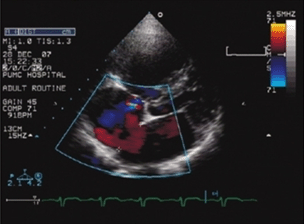

心 脏彩超是唯一能动态显示心腔内结构、心脏的搏动和血液流动的仪器,对人体没有任何损伤。心脏探头就像摄像机的镜头,随着探头的转动,心脏的各个结构清晰地 显示在屏幕上。比如先天性心脏病,其总数不下于100种的畸形都能用心脏彩超显示出来。我们能在屏幕上看到残留的孔洞以及通过该孔的血流;能看到瓣膜的增 厚、开口减小及通过该瓣口的高速血流;能看到心脏结构左、右及前、后位置上的变化,以及由此造成的血流路径的改变;能看到异常位置的心脏伴发的各种畸形。

4、评价心脏血流动力学变化,多普勒常规测量各瓣口流速和压差,判断心血管内异常血流部位和起源,定量或半定量分流、流出道狭窄、瓣膜狭窄和反流等异常血流的流速、压差及流量等。